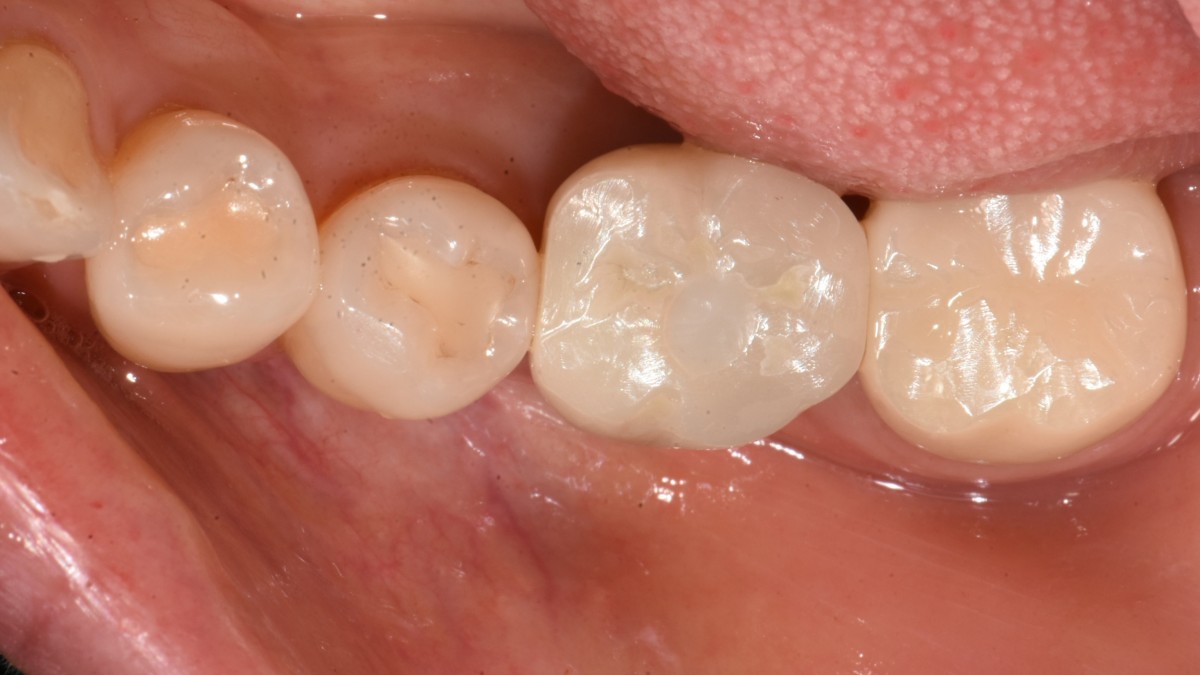

Immediate placement of an implant (Arum Dnetistry NB1, 5*8.5)

Immediate placement of an implant

Extraction and immediate placement of an implant.